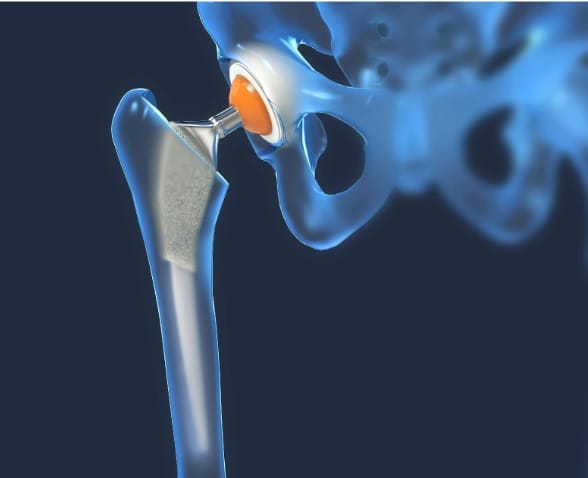

هذا الشق الجراحي سيتخلل طبقات الأنسجة، سامحًا للطبيب بإزالة الغضاريف والعظام المصابة والتالفة، مع التركيز على عدم المساس بما هو سليم منها، وبعد الانتهاء من هذه الخطوة يُزرع التجويف البديل الذي يحل محل الجزء العلوي من المفصل أعلى عظمة الفخذ، وفي النهاية يتم إدخال الجذع داخل عظام الفخذ العلوية، وتوضع فوقه الكرة البديلة التي تُحاكي حركة المفصل، ويتم في النهاية خياطة الجرح وتضميده جيدًا.

أحدث ما تم التوصل إليه من خاماتٍ لصناعة مفصل الحوض البديل هو التيتانيوم والسيراميك، ولهذه الخامات القدرة على تقليل فرص تآكل العظام واحتكاكها بنسبة كبيرة، مع احتمالات تكاد تنعدم لخلع المفصل وخروجه من مكانه.